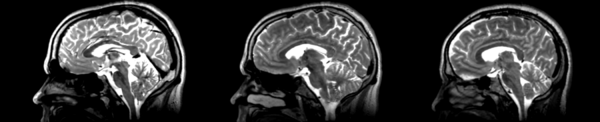

- 01053-t2 -> 01031-t2 = Result. All the images shown have the moving image on the left, the resultant image in the middle, and the target image on the right.

Rigid

01053>01031rigid.png = not bad... different brains of different sizes, but seem to be aligned in the ventricles so output seems okay. output slightly blurry. bad initial leveling displays.

Linear

01053>01031linear.png = not bad... different brains of different sizes, but seem to be aligned in the ventricles so output seems okay.output slightly blurry. bad initial leveling displays.

Affine

01053>01031_affine.png = looks good in terms of size. odd warping of frontal lobe and cerebellum area, but otherwise good coregistration.